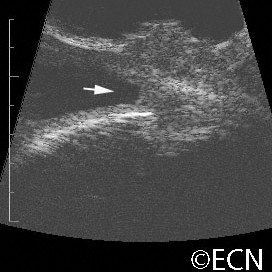

Brawny scleritis

Brawny scleritis - 10 MHz B-scan ultrasound reveals thickening of the sclera and vitreous cells (arrow).